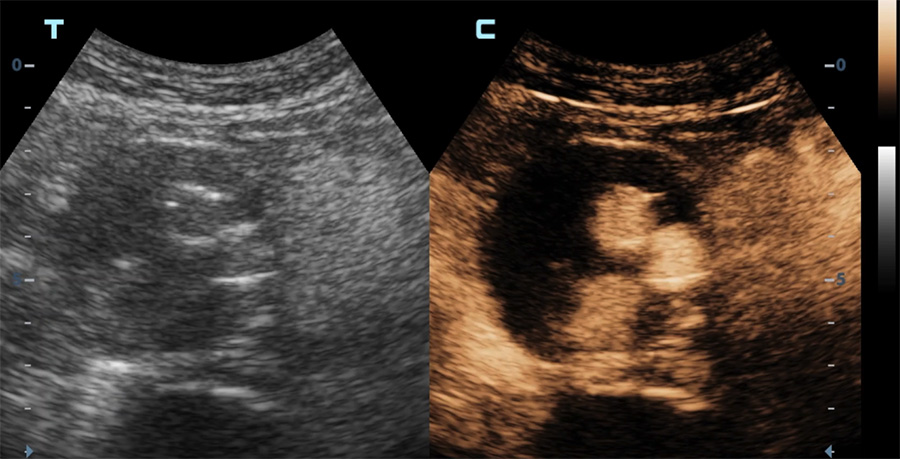

Echographie en mode contraste d’une endoprothèse aortique

Apparition du produit de contraste dans la lumière des vaisseaux

Diffusion du produit de contraste dans le sac anévrismal (vue axiale) en dehors de l’endoprothèse (endofuite)